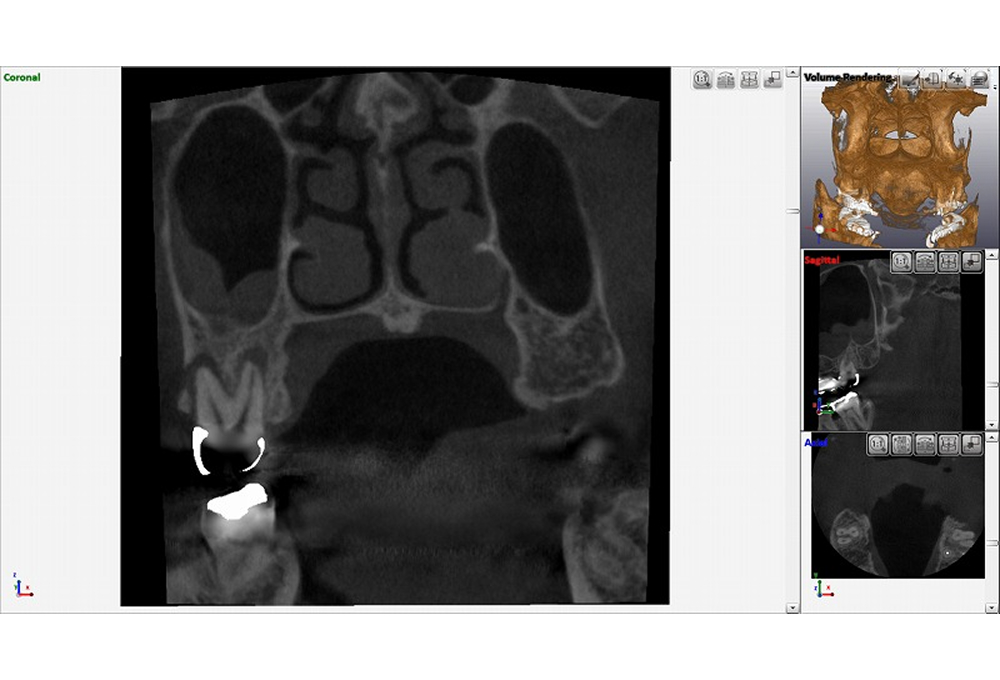

②CTで上顎洞粘膜肥厚 根尖病変確認